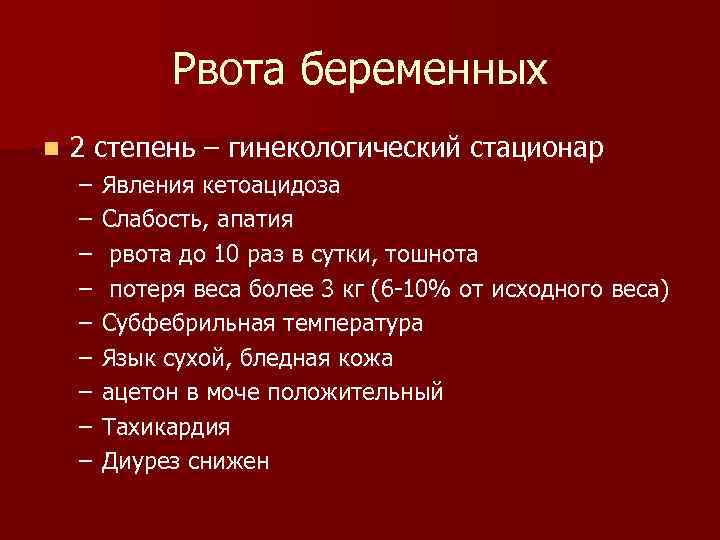

Рвота беременных n 2 степень – гинекологический стационар – – – – – Явления кетоацидоза Слабость, апатия рвота до 10 раз в сутки, тошнота потеря веса более 3 кг (6 -10% от исходного веса) Субфебрильная температура Язык сухой, бледная кожа ацетон в моче положительный Тахикардия Диурез снижен

Рвота беременных n 2 степень – гинекологический стационар – – – – – Явления кетоацидоза Слабость, апатия рвота до 10 раз в сутки, тошнота потеря веса более 3 кг (6 -10% от исходного веса) Субфебрильная температура Язык сухой, бледная кожа ацетон в моче положительный Тахикардия Диурез снижен